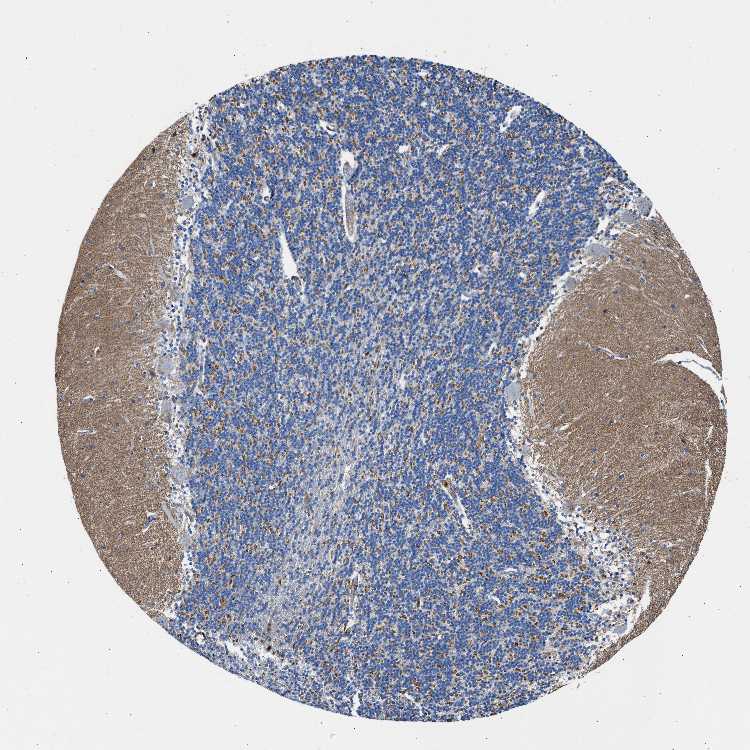

CEREBELLUM - Antibody stainingi

Antibody staining in the annotated cell types in the current human tissue is reported as not detected, low, medium, or high, based on conventional immunohistochemistry profiling in selected tissues. This score is based on the combination of the staining intensity and fraction of stained cells.

Each image is clickable and will lead to virtual microscopy that enables deeper exploration of all samples and also displays staining intensity scores, fraction scores and subcellular localization as well as patient and tissue information for each sample.

Antibody HPA016938

Purkinje cells Not detected

Cells in granular layer Low

Cells in molecular layer Not detected